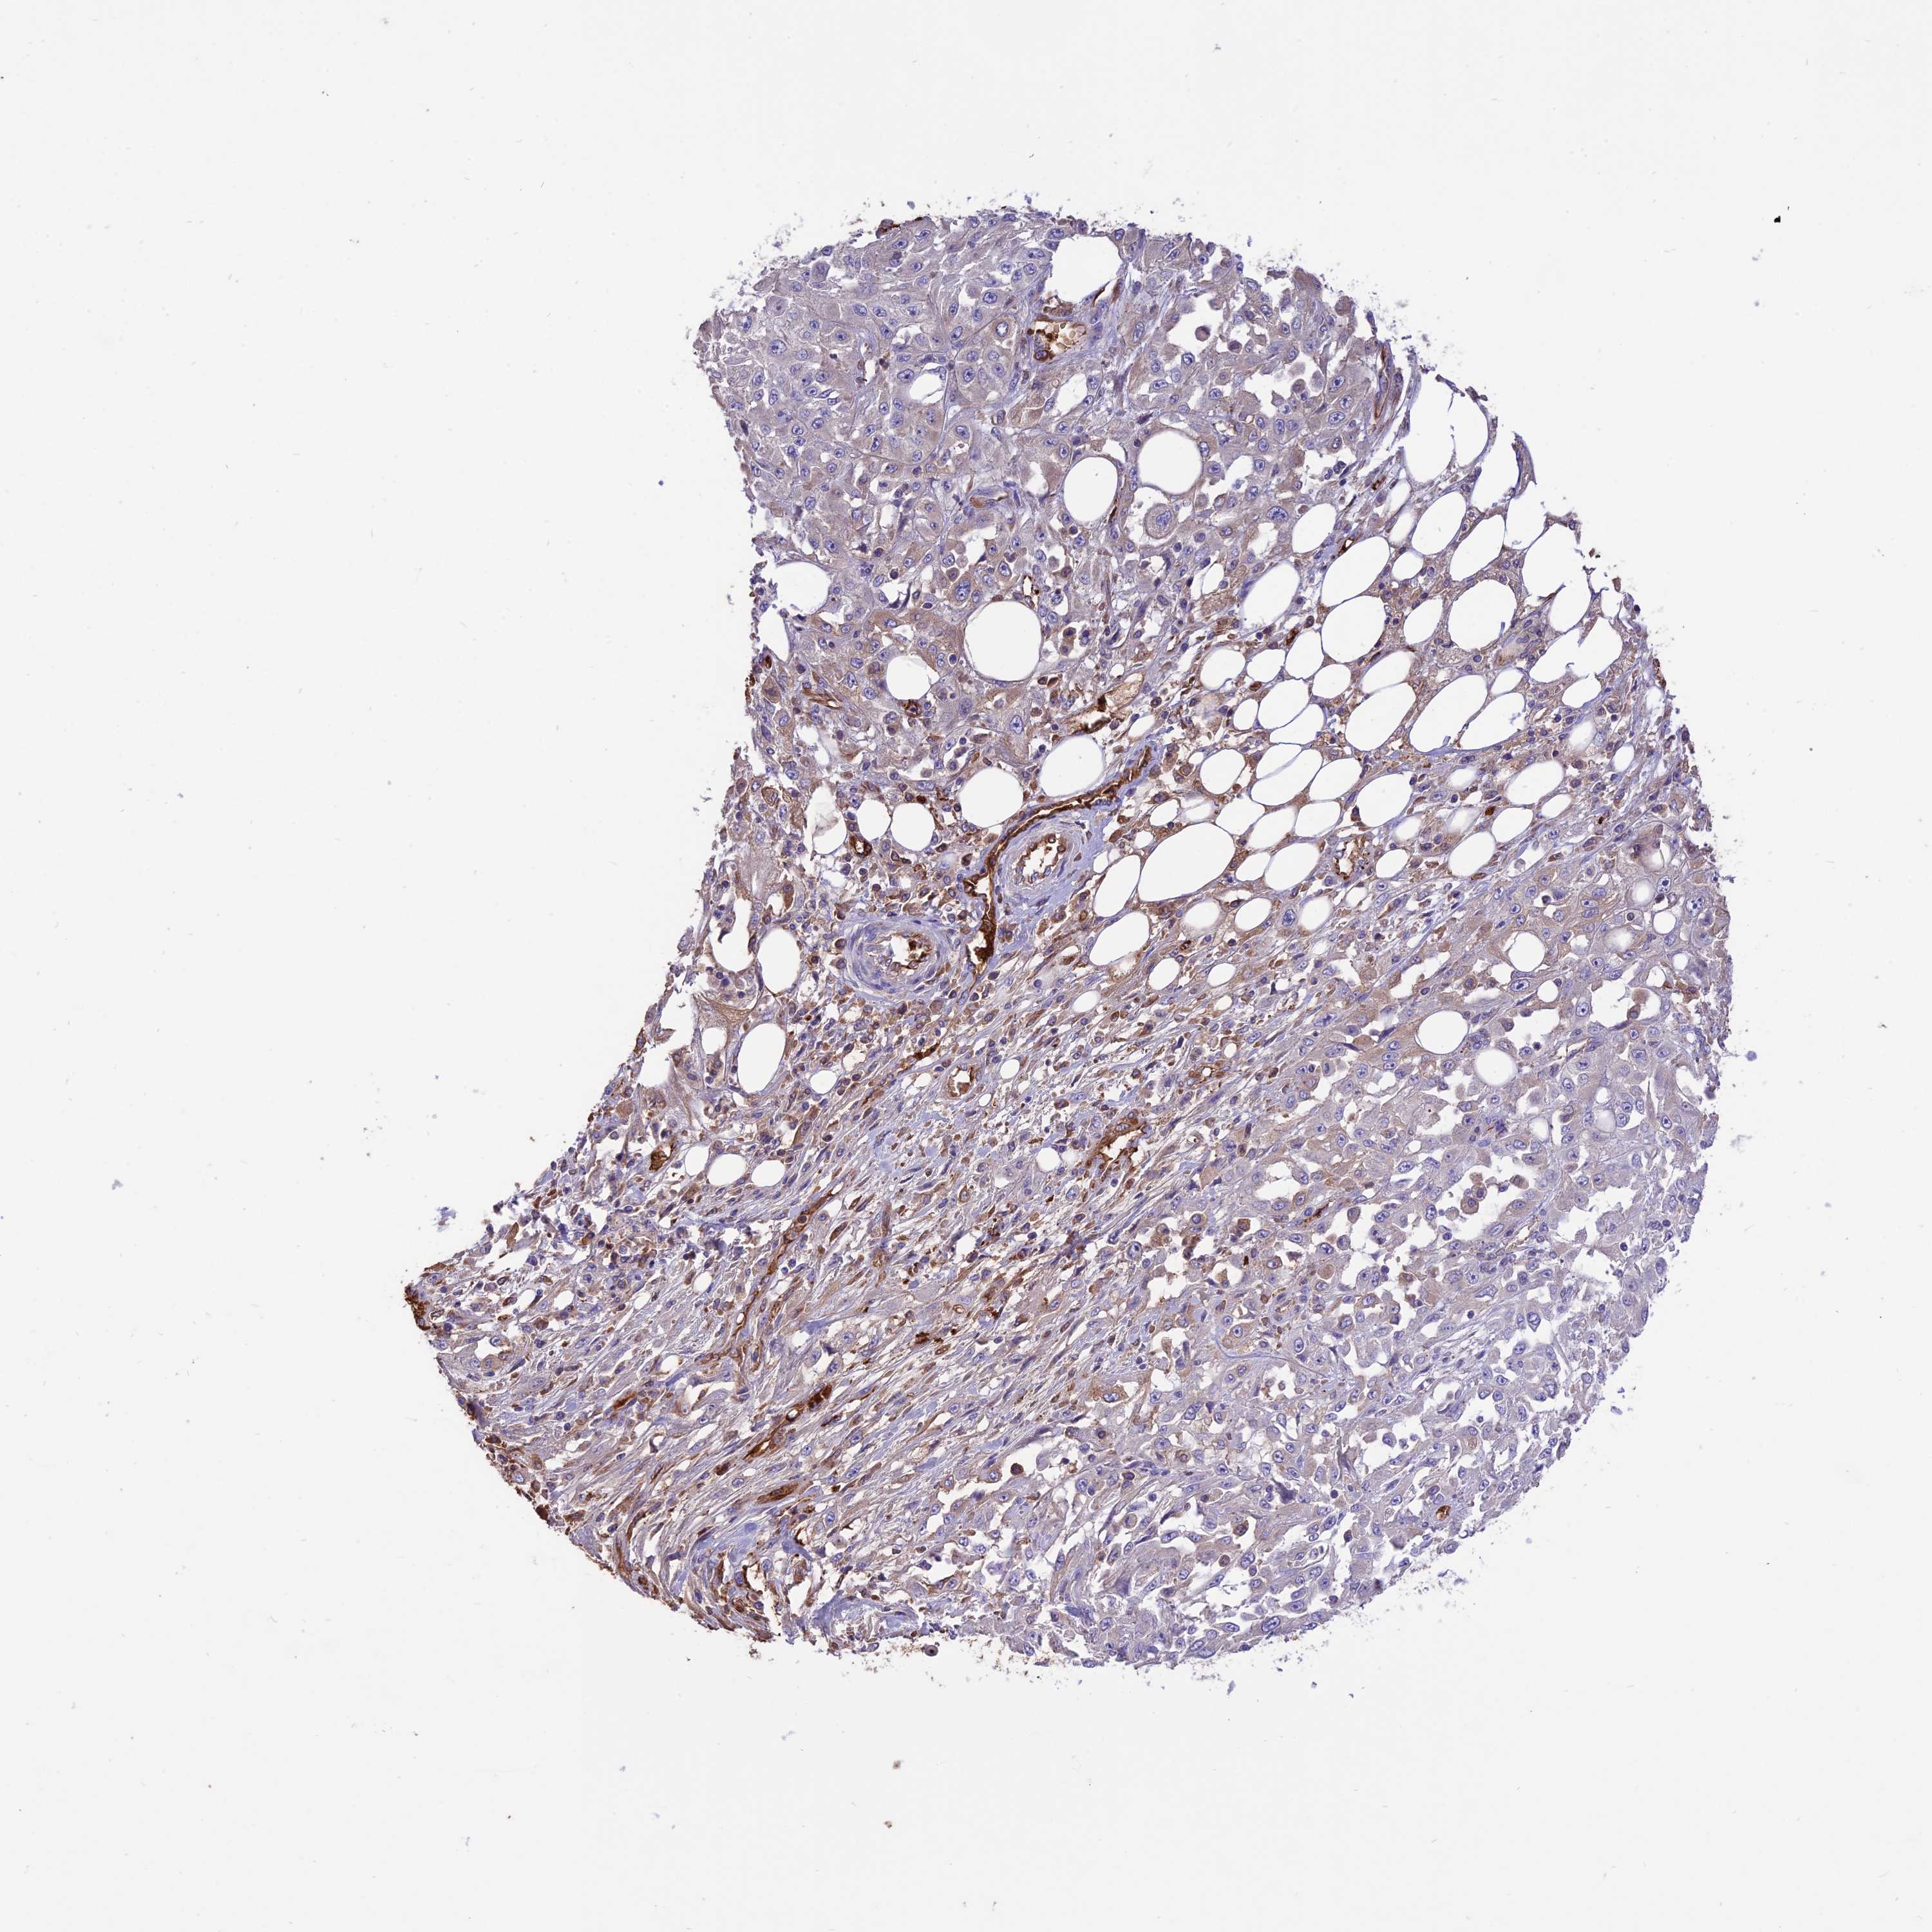

SKIN CANCER - Protein expressioni

A mouse-over function shows sample information and annotation data. Click on an image to view it in a full screen mode. Samples can be filtered based on level of antibody staining by selecting one or several of the following categories: high, medium, low and not detected. The assay and annotation is described here.

Each image is clickable and will lead to virtual microscopy that enables deeper exploration of all samples and also displays staining intensity scores, fraction scores and subcellular localization as well as patient and tissue information for each sample.

Antibody HPA041608

Basal cell carcinoma